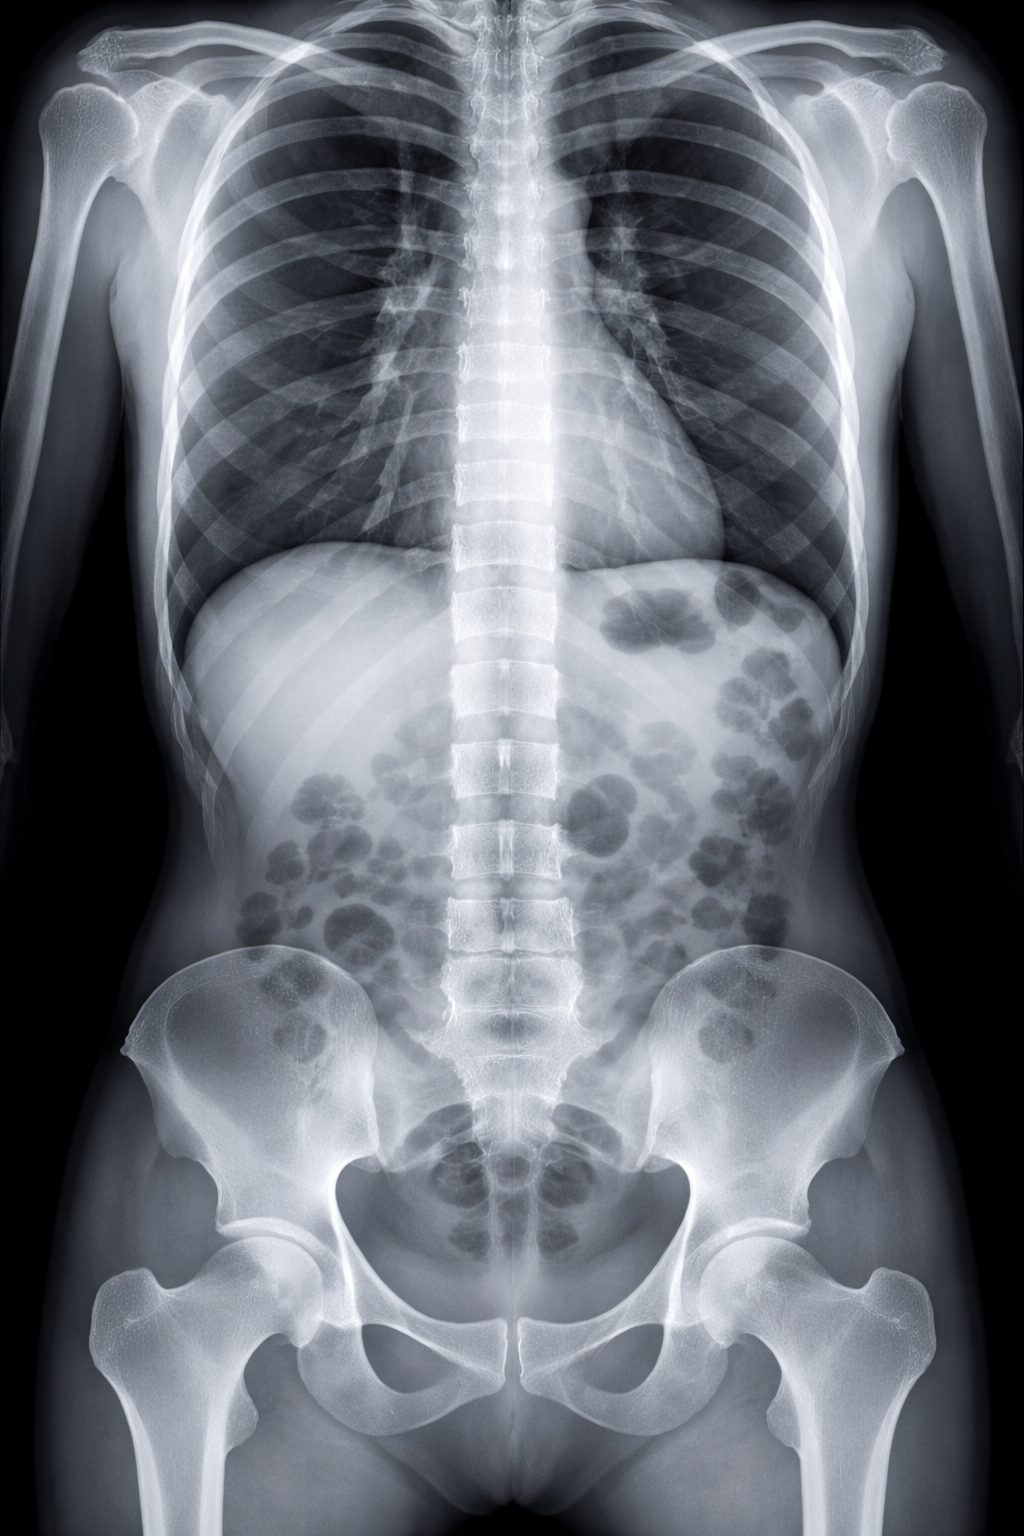

Une radiographie standard, communément désignée sous le terme de radiographie conventionnelle ou radiographie X, constitue une méthode d'imagerie médicale largement employée pour examiner l'intérieur du corps humain.

Cette technique repose sur l'utilisation de rayons X, des radiations ionisantes, afin de produire des images bidimensionnelles des structures internes. Lors de l'examen, le patient se situe devant un détecteur de rayons X, pendant que le générateur de rayons X émet des photons à travers la zone corporelle à évaluer.

Les divers tissus corporels absorbent les rayons X à des degrés variés en fonction de leur densité, engendrant ainsi des ombres sur le détecteur. Ces ombres se traduisent par une image radiographique, où les os apparaissent plus lumineux du fait de leur capacité à absorber plus intensément les rayons X, tandis que les tissus mous se manifestent de manière plus sombre.

Les radiographies standards sont fréquemment utilisées dans le diagnostic de diverses pathologies, telles que les fractures osseuses, les infections, les obstructions, ainsi que pour orienter certaines procédures médicales.